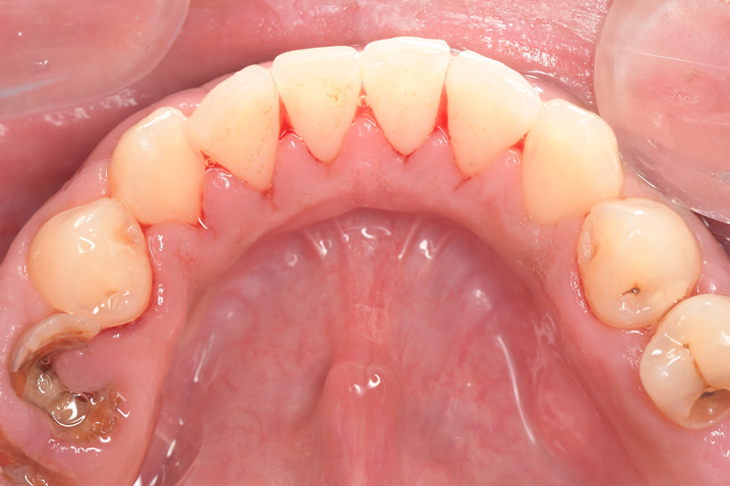

Before①

| 主訴 | 下顎 歯石除去したい |

| 治療内容 | スケーリング |

| 治療期間 | 30分 |

| 治療費 | 約1,500円(保険診療) |

| リスク・副作用 | 知覚過敏、歯肉退縮 |

| 治療方針 | 歯肉縁上歯石を除去してから歯肉縁下歯石を除去します。ご自身でのプラークコントロールができるようになったら定期検診に移行します。 |

| 担当者所見 | 半年ぶりの歯科医院の受診。歯石が付きやすいためセルフケアの重要性をお伝えして、定期的にクリーニングを行います。出血率が高く炎症が強いため、今後はセルフケアを強化して歯周病治療を行います。 |